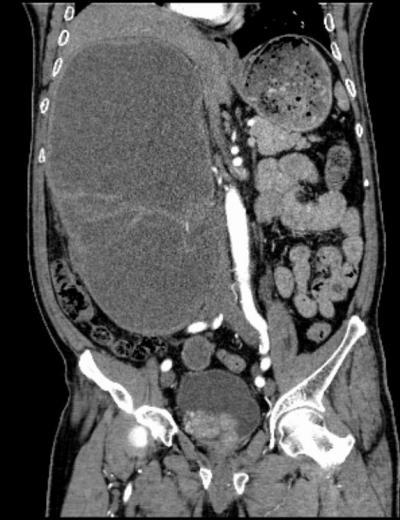

入院后,科室为患者完善影像学、内镜及病理等一系列检查,明确诊断其右肾盂、右输尿管及膀胱均存在恶性肿瘤病灶,其中右输尿管肿瘤引发梗阻,导致右肾严重积水,肾脏体积达650px×500px×175px,病情复杂程度远超常规病例,常规治疗方案难以达到理想疗效。

2026年1月底,患者完成新辅助治疗后,经评估手术条件已成熟,且患者及家属手术意愿明确。在麻醉科、手术室护理团队的全力配合下,李化升主任带领手术团队开始手术。为建立有效操作空间,团队先为患者穿刺抽出3600ml血性尿液,使肿大的肾脏体积有所缩小,随后开展腹腔镜下右肾切除操作。术中发现肾脏与十二指肠等周围组织严重粘连,腔镜下仅能游离约85%,团队随即调整方案,通过开放手术游离剩余部分并顺利取出肾脏。